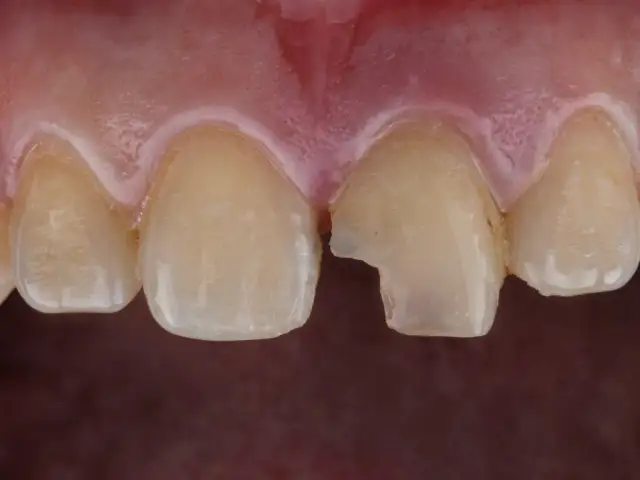

Domowe sposoby na próchnicę? Dowiedz się, jak remineralizować szkliwo i kiedy wizyta u dentysty jest niezbędna. Odkryj nowoczesne metody leczenia.